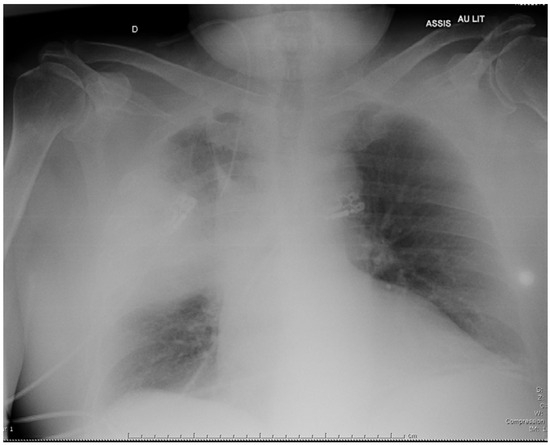

Introduction: Legionella micdadei are gram-negative bacilli living in soil and aquatic habitats. They are responsible for less than 10% of legionellosis, but have a propensity to affect people suffering from immunodeficiency. Lung cavitations may also occur in this population. Isolation of L. micdadei on clinical samples requires specific culture media that are not routinely used. Moreover, serologic methods and urinary assays are specific for Legionella pneumophila serogroup 1 (the most frequent serogroup isolated from clinical specimens), and lack sensitivity for diagnosing L. micdadei infection. As a consequence, this diagnosis is difficult to confirm. Case report: We report here a severe case of community-acquired legionellosis due to L. micdadei, in a patient under immunosuppressive medications and high-dose corticosteroids for rheumatoid arthritis. The source of his infection was hypothesized to be his continuous positive airway pressure device, which was regularly cleaned with tap water instead of sterile water, thus potentially resulting in Legionella contamination. Conclusions: L. micdadei must be considered as a possible cause of community-acquired severe pneumonia in case of immunodeficiency. For outpatients, advice concerning the cleaning of aerosols-generating devices at home must be emphasized. Full article